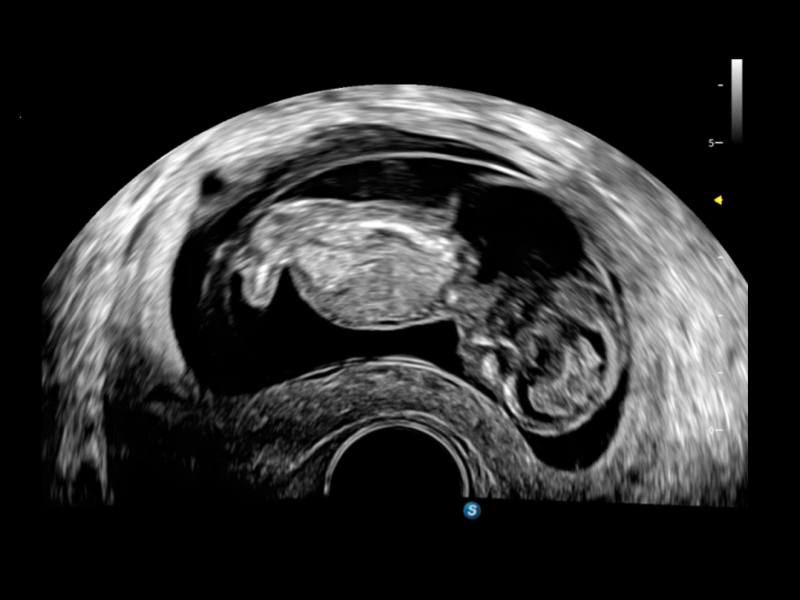

作为开立医疗全新打造的超高端旗舰超声产品,从探头抬起唤醒开启扫查到多维探头发射接收,通过先进的场成像发射、自适应聚合重建等技术,基于RF Data原始射频数据在图像生成、高端功能等方面实现突破,提供多科室综合临床解决方案。

S80 提供多样化超声成像技术,可满足不同科室的需求,在助力扫查诊断和介入治疗中发挥着重要作用。

提供解剖示意图、标准超声图像、扫查手法图和操作者实时检查图像,指导操作者进行标准切面的正确扫查。